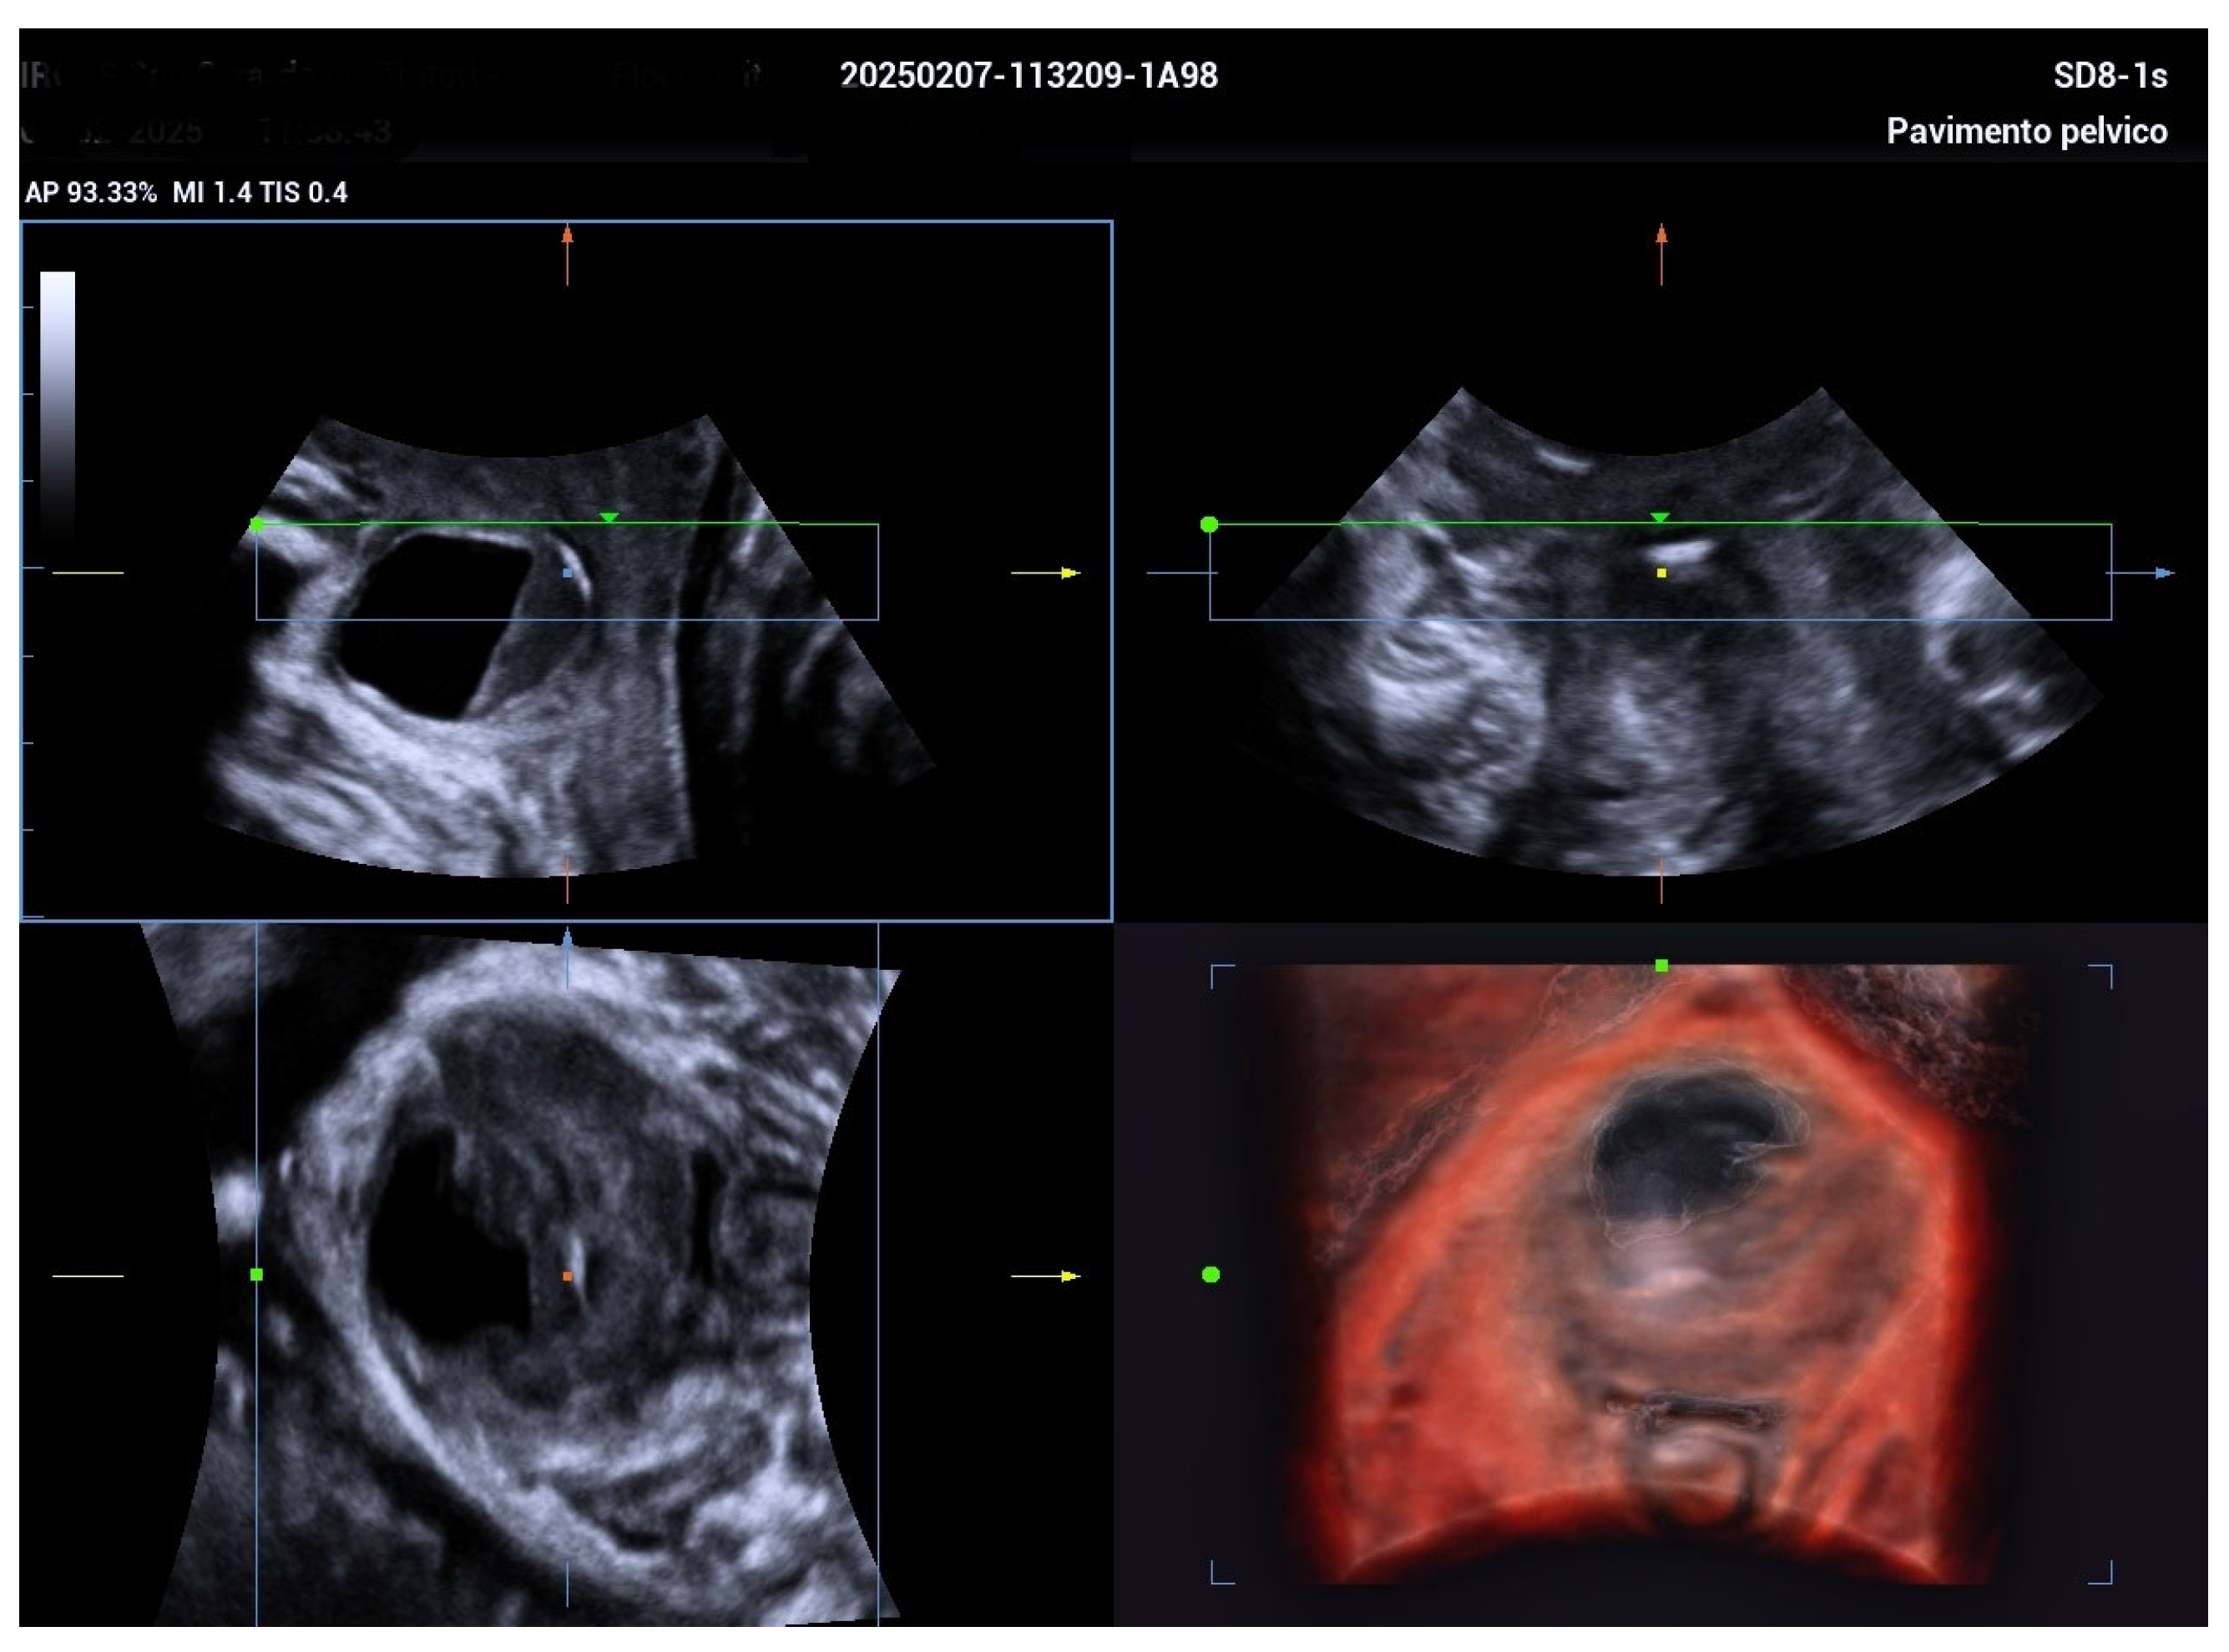

Managing Urethral Diverticulum During Pregnancy Utilizing Advanced Ultrasonographic Techniques: A Literature Review and Case Study

2. Case Report

| Jeong et al. [5] | Suprapubic pain, purulent discharge, leakage | 5.5 cm | TVUS, TPUS, 3D ultrasound at 34 weeks | Antibiotics; aspiration considered | Planned vaginal delivery | Postpartum diverticulectomy |